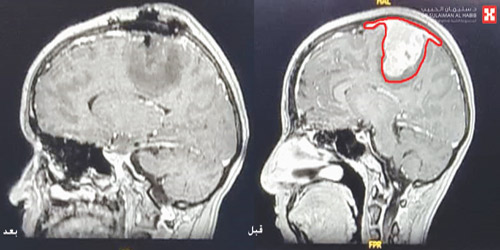

وقال الدكتور مسعود إنه اتضح أن المريضة عانت قبل 3 أسابيع من وصولها للمستشفى من تشنجات بسيطة زادت حدتها بمرور الأيام الأولى، حتى أصيبت بشلل في الجزء الأيمن من الجسم بالأطراف العلوية والسفلية، وتعرضت لنوبات شديدة من الصرع. وأشار إلى أن نتائج الفحوصات كشفت عن وجود ورم ضخم متمركز في الجزء الأيسر من الدماغ يضغط على مراكز الحركة، كما أنه متغلغل في أكبر وأعمق وريد بالمخ وهو المسؤول عن نقل الدم إلى كامل الدماغ والمعروف باسم (Sagittal Sinus)، كما بين فحص تخطيط الدماغ وجود شحنات كهربائية عالية حول منطقة الورم، وهو الأمر الذي يفسر حدوث الشلل بالجزء الأيمن من الجسم، وكذلك تعرضها لمثل هذه النوبات الصرعية الحادة.

وأفاد د. مسعود بأن جهود الفريق الطبي تكللت بالنجاح ولله الحمد، وتم إزالة أجهزة التنفس بعد العملية مباشرة مع تحسن المؤشرات الحيوية، والتأكد من سلامة مراكز الحركة بالمخ، واستطاعت المريضة تحريك أطرافها العلوية والسفلية بعد 4 ساعات فقط بعد العملية، وفي اليوم الثالث نقلت إلى جناح التنويم وخرجت في اليوم الرابع مع وضع برنامج علاج طبيعي مكثف لتقوية العضلات، مشيراً إلى أنه تم متابعتها في العيادة خلال 3 أسابيع وقد تحسنت حالتها بشكل كامل، وعادت لتمارس حياتها بصورة طبيعية.